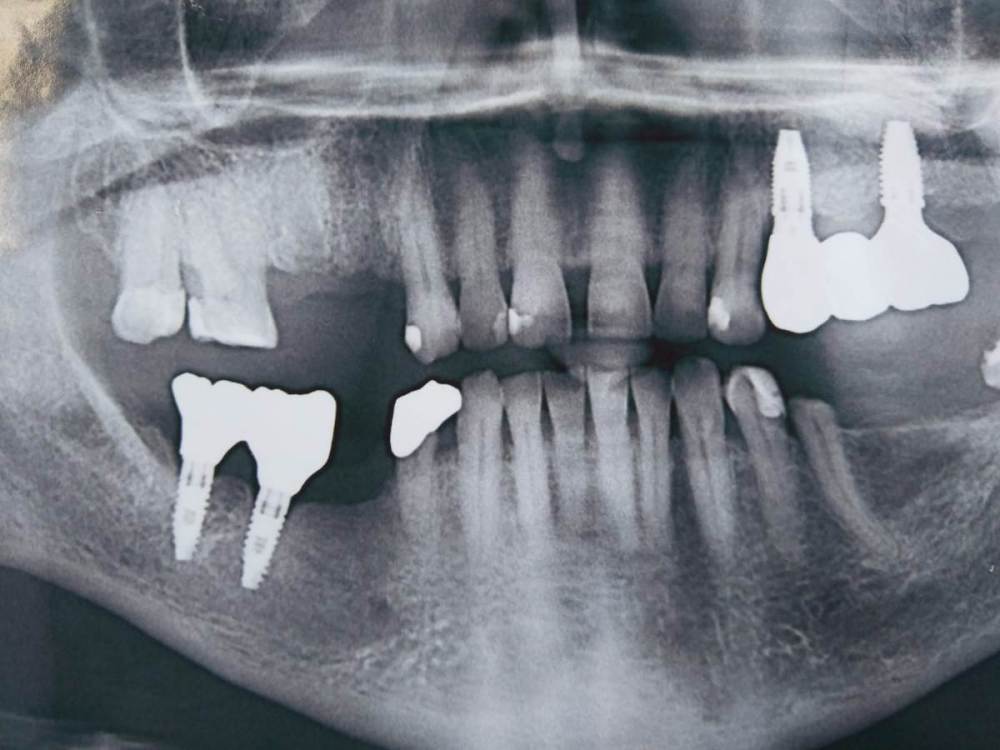

ssmokie Опубликовано 30 октября, 2023 Поделиться Опубликовано 30 октября, 2023 (изменено) Добрый день всем. Пациент Ж 70лет Ситуация - подготовка к имплантации верхних правых 4,5. Нижней правой 5. Верхние правые 6, 7, внешне в хорошем состоянии не считая корневого кариеса на 6 со стороны 7. Вариант 1. Оставить 6 если кто-то возьмется его вылечить, кариес заходит ниже уровня десны. Вариант 2. Удалить 6 и уже вставлять импланты на 4,6 и 3 коронки. Хочется сохранить 6ку если это целесообразно и возможно. Может быть с коронкой на корень например. В районной поликлинике такое лечить отказались. Может, кто-то возьмется или посоветует доктора в Санкт-Петербурге. Если возможно оцените примерную стоимость работы по лечению пожалуйста, тк от этого зависит есть-ли экономический смысл лечить или сразу ставить 3 коронки на 2 импланта. Изменено 30 октября, 2023 пользователем ssmokie Ссылка на комментарий

АнтонТЛТ Опубликовано 30 октября, 2023 Поделиться Опубликовано 30 октября, 2023 Удалить и поставить имплантаты как слева 4, 6 3 Ссылка на комментарий